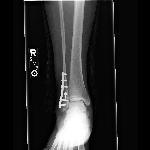

On the outside of my leg, an angry-looking five inch scar ran from the lower calve to the top of my foot. Stitches poked out at random intervals like little weeds in a garden row. And where did the bone go? The little round anklebone that should jut out a bit? GONE.

“It’s…it’s…” I sniffed “It looks like Franken-ankle!” That’s what it looked like to me.

As for what now holds my leg together? One titanium plate, six screws and one pin. In the grand scheme of things, it’s not a big deal. I am learning to reach for the hem of Jesus’ garment for His healing, and His will, instead of reaching out to ask Him “why”.